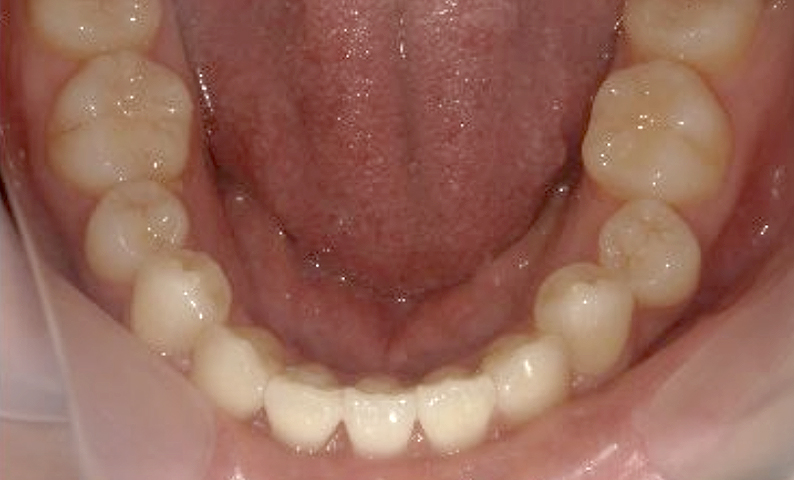

症例_025 上下顎の部分矯正

治療期間:13ヶ月金額:51万円+税女性前歯のガタガタ出っ歯